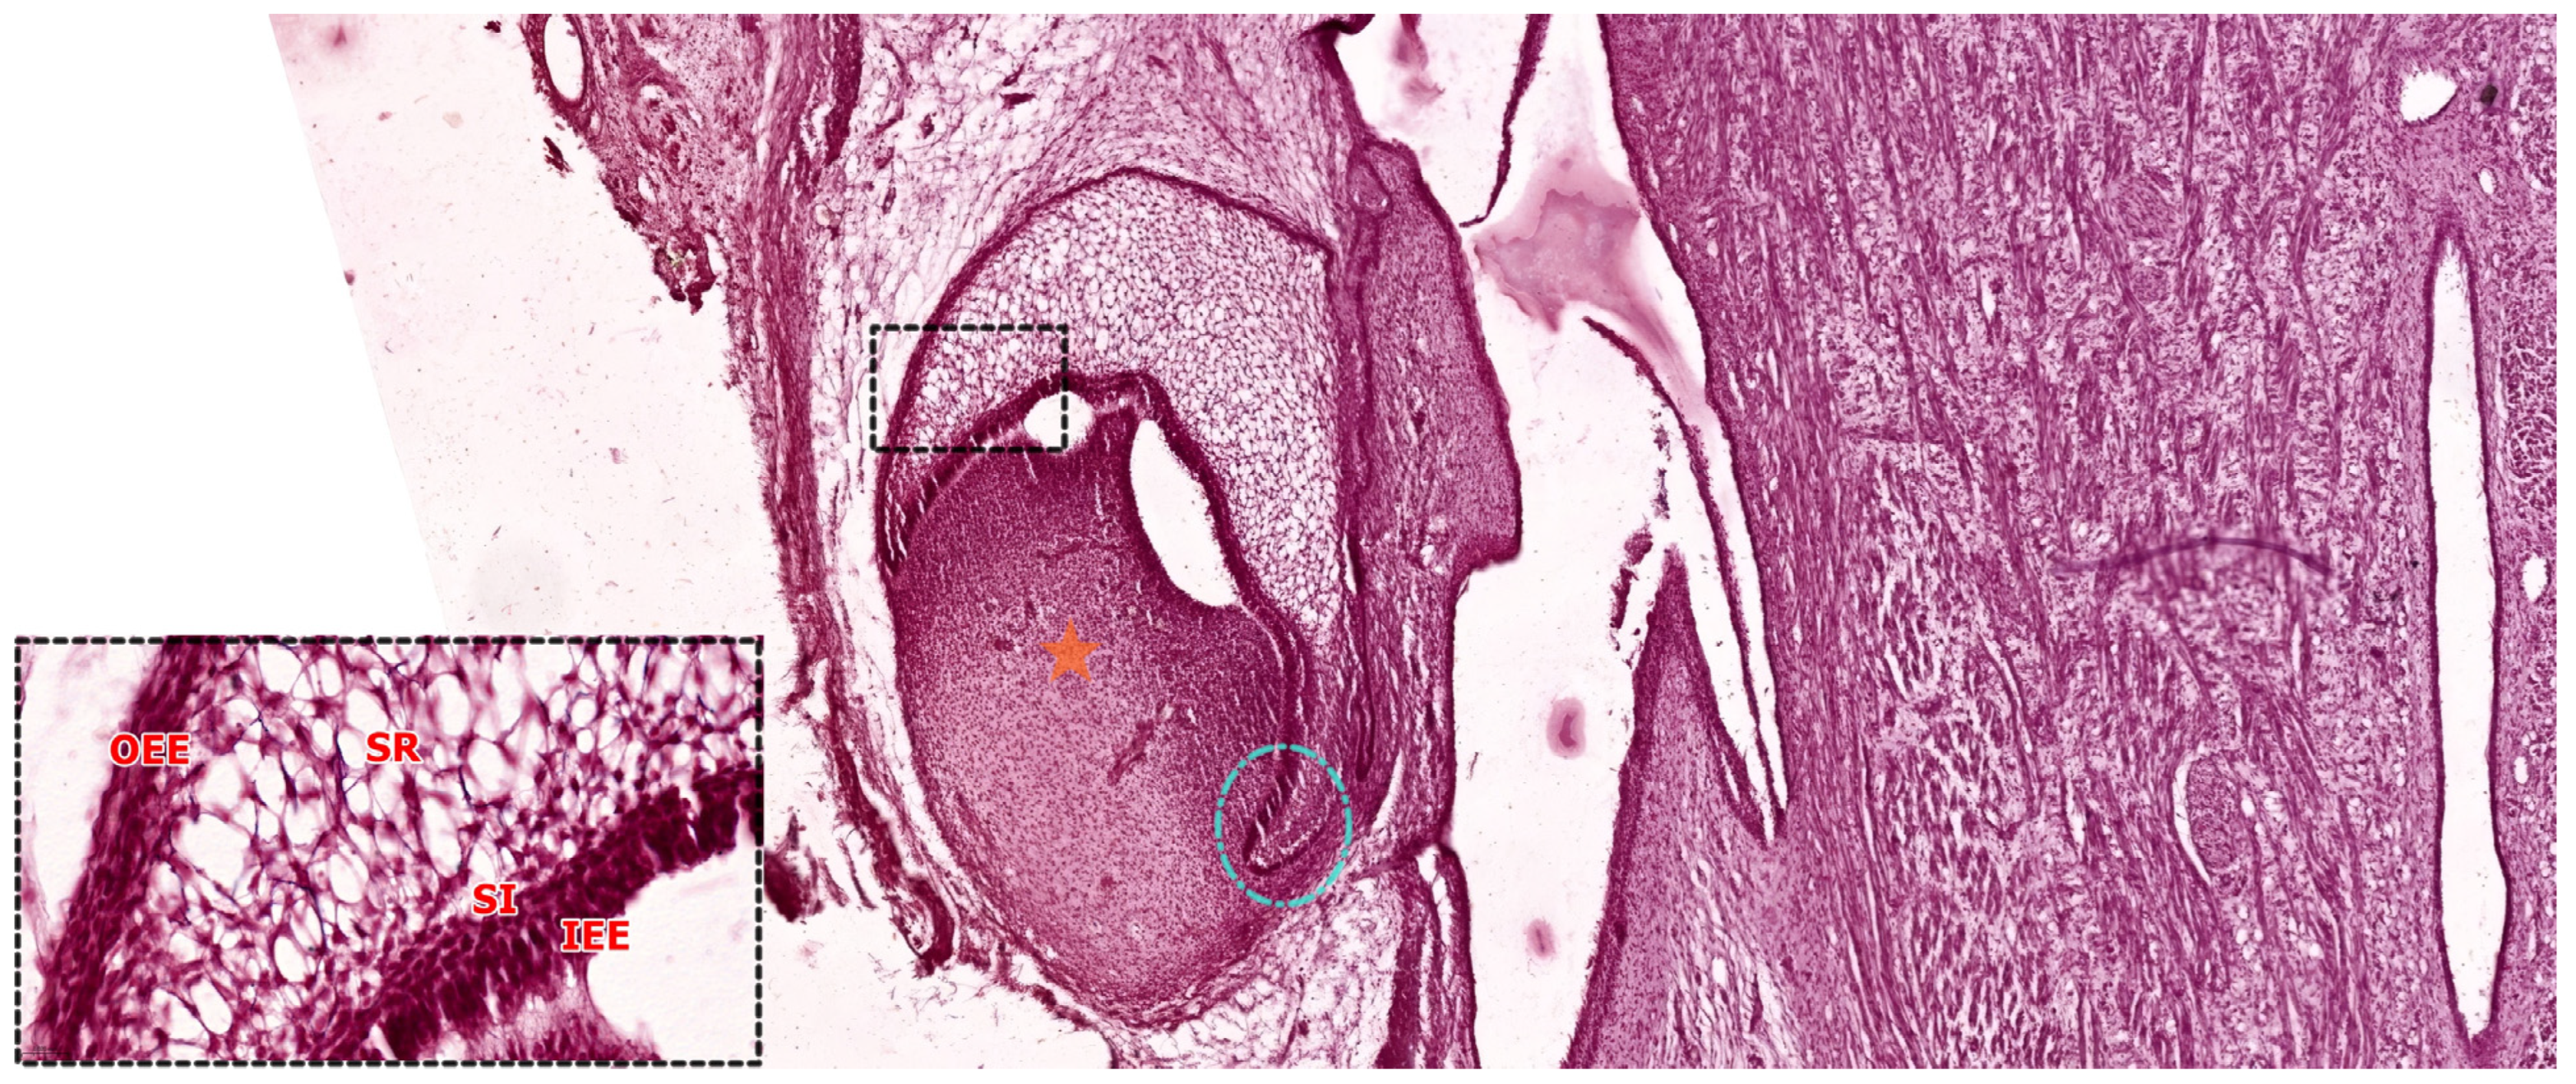

3.3. The Bell Stage

3.3.1. Early Bell Stage